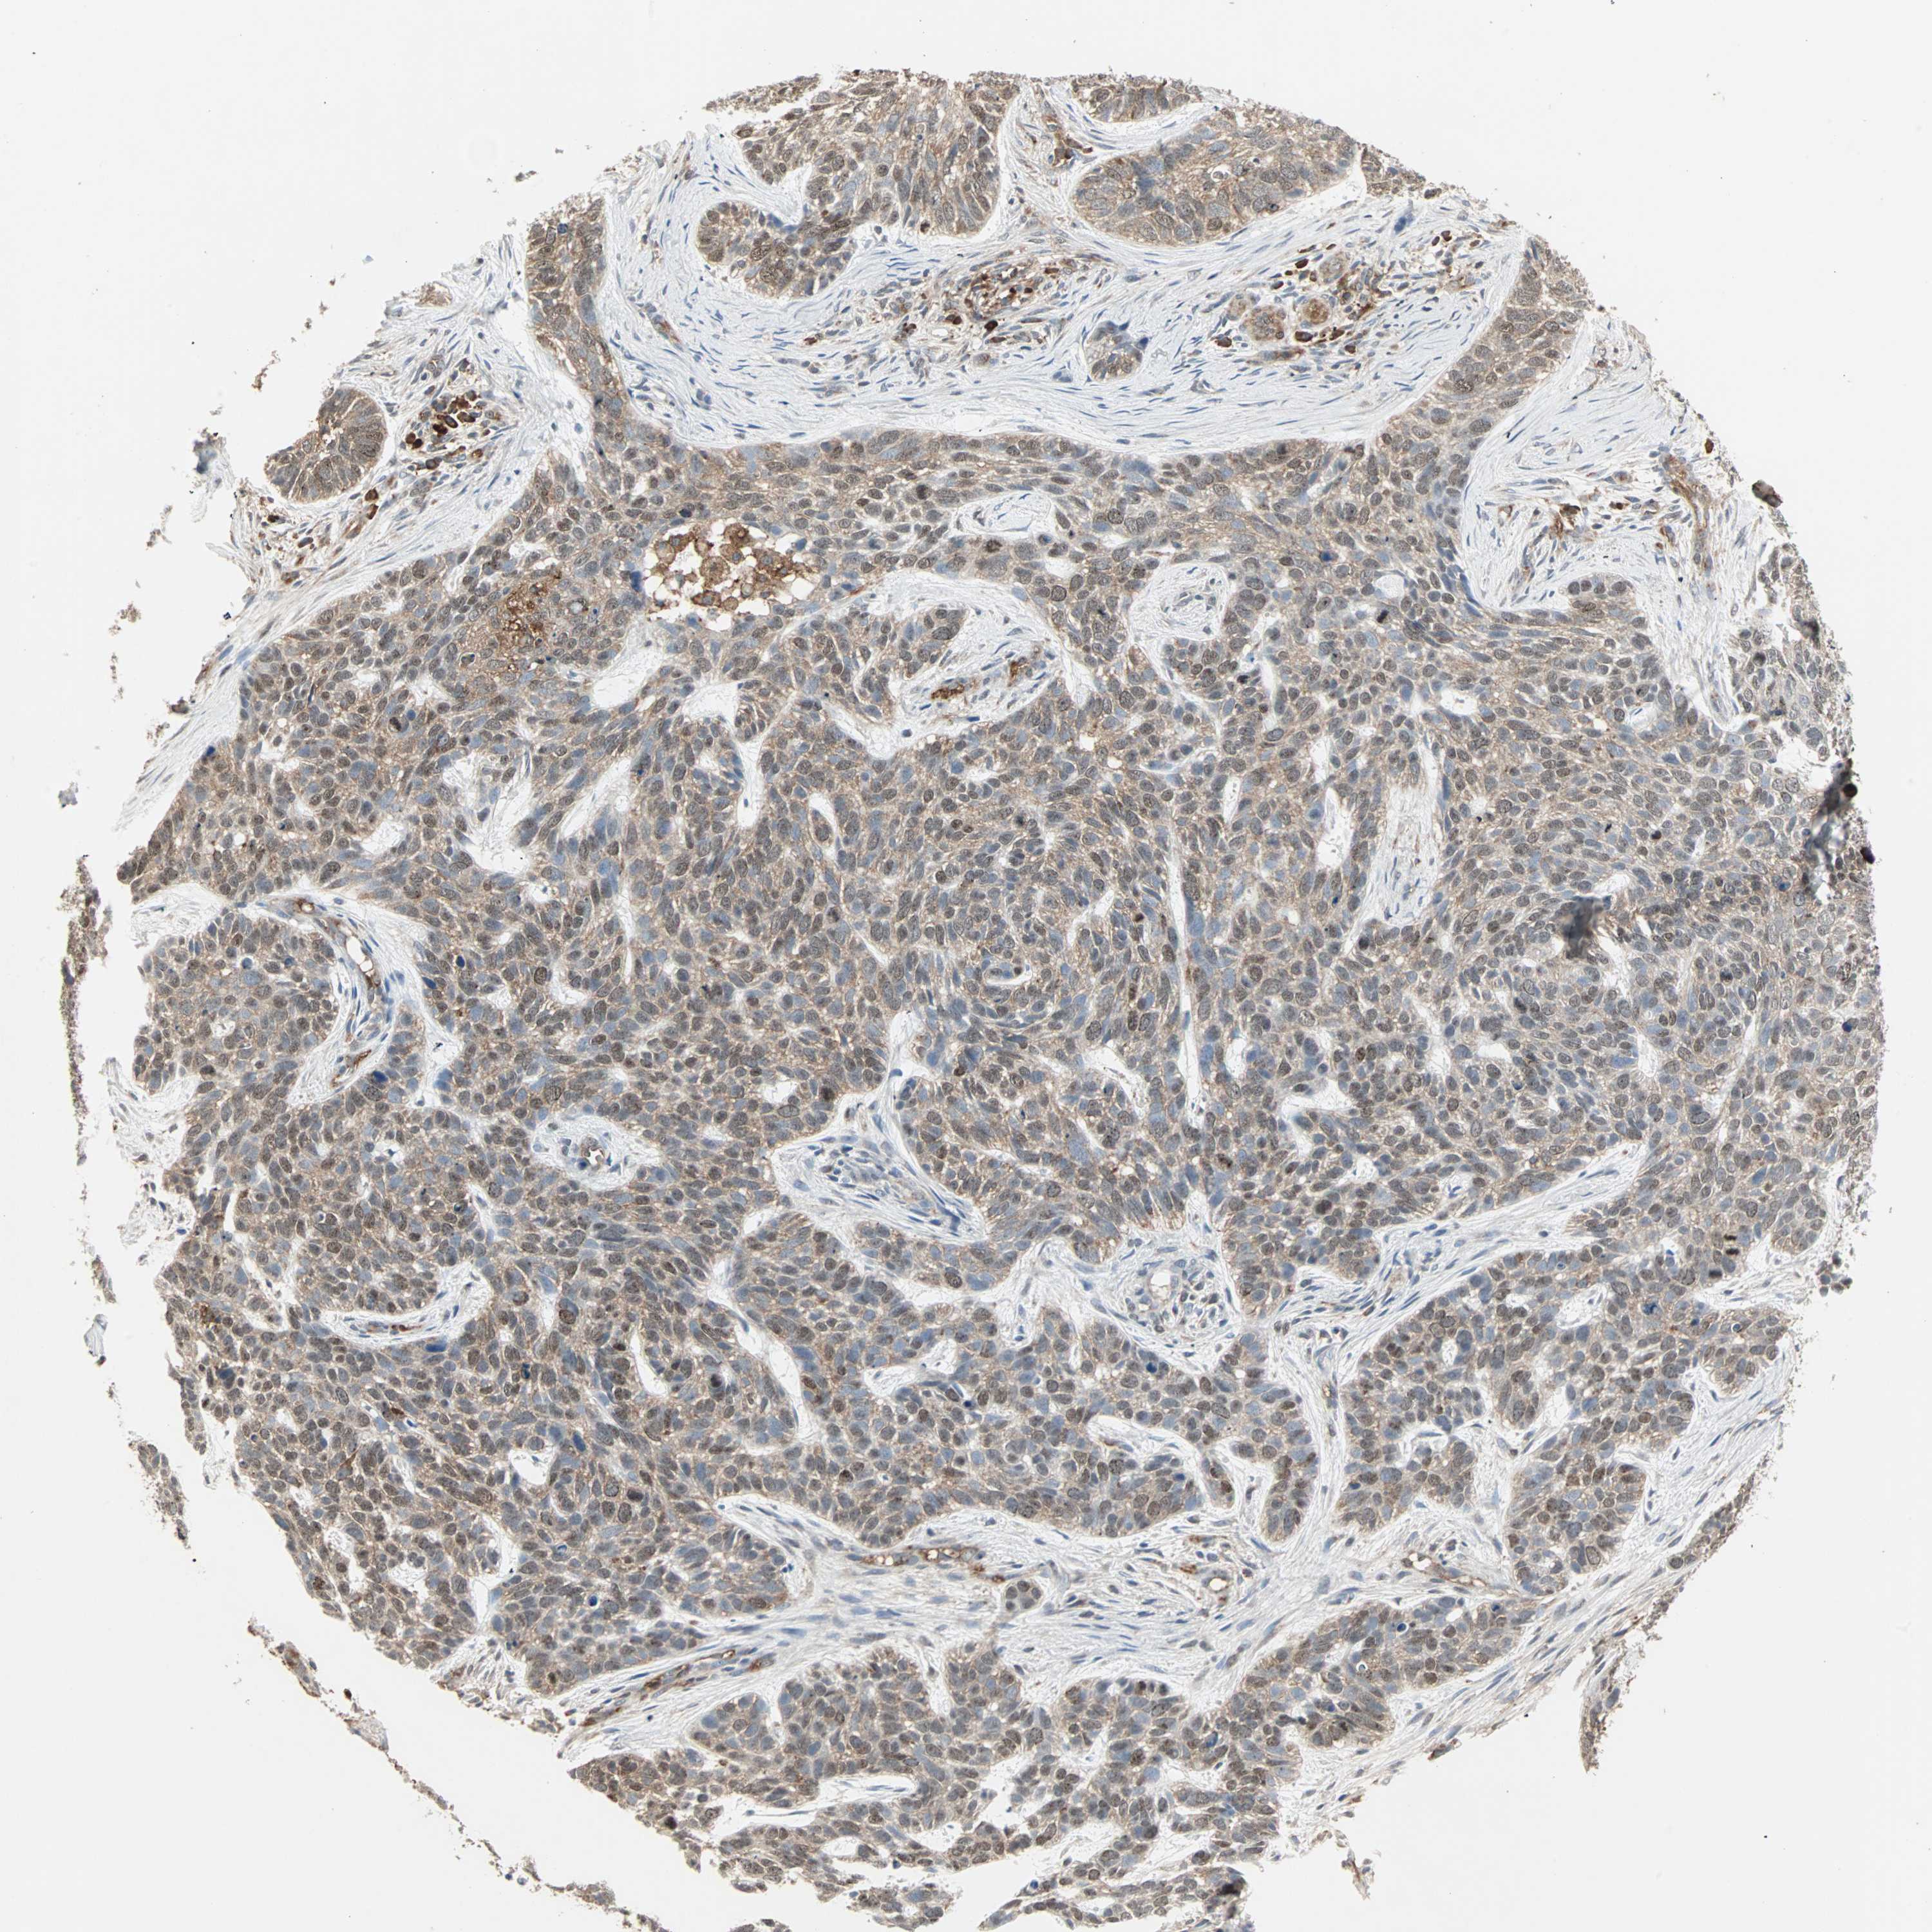

SKIN CANCER - Protein expressioni

A mouse-over function shows sample information and annotation data. Click on an image to view it in a full screen mode. Samples can be filtered based on level of antibody staining by selecting one or several of the following categories: high, medium, low and not detected. The assay and annotation is described here.

Antibody stainingi

Antibody staining in the annotated cell types in the current human tissue is reported as not detected, low, medium, or high, based on conventional immunohistochemistry profiling in selected tissues. This score is based on the combination of the staining intensity and fraction of stained cells.

Each image is clickable and will lead to virtual microscopy that enables deeper exploration of all samples and also displays staining intensity scores, fraction scores and subcellular localization as well as patient and tissue information for each sample.

Antibody HPA007875

Staining

High

Medium

Low

Not detected

Intensity

Strong

Moderate

Weak

Negative

Quantity

>75%

75%-25%

<25%

None

Location

Nuclear

Cytoplasmic/membranous

Cytoplasmic/membranous,nuclear

Squamous cell carcinoma, NOS